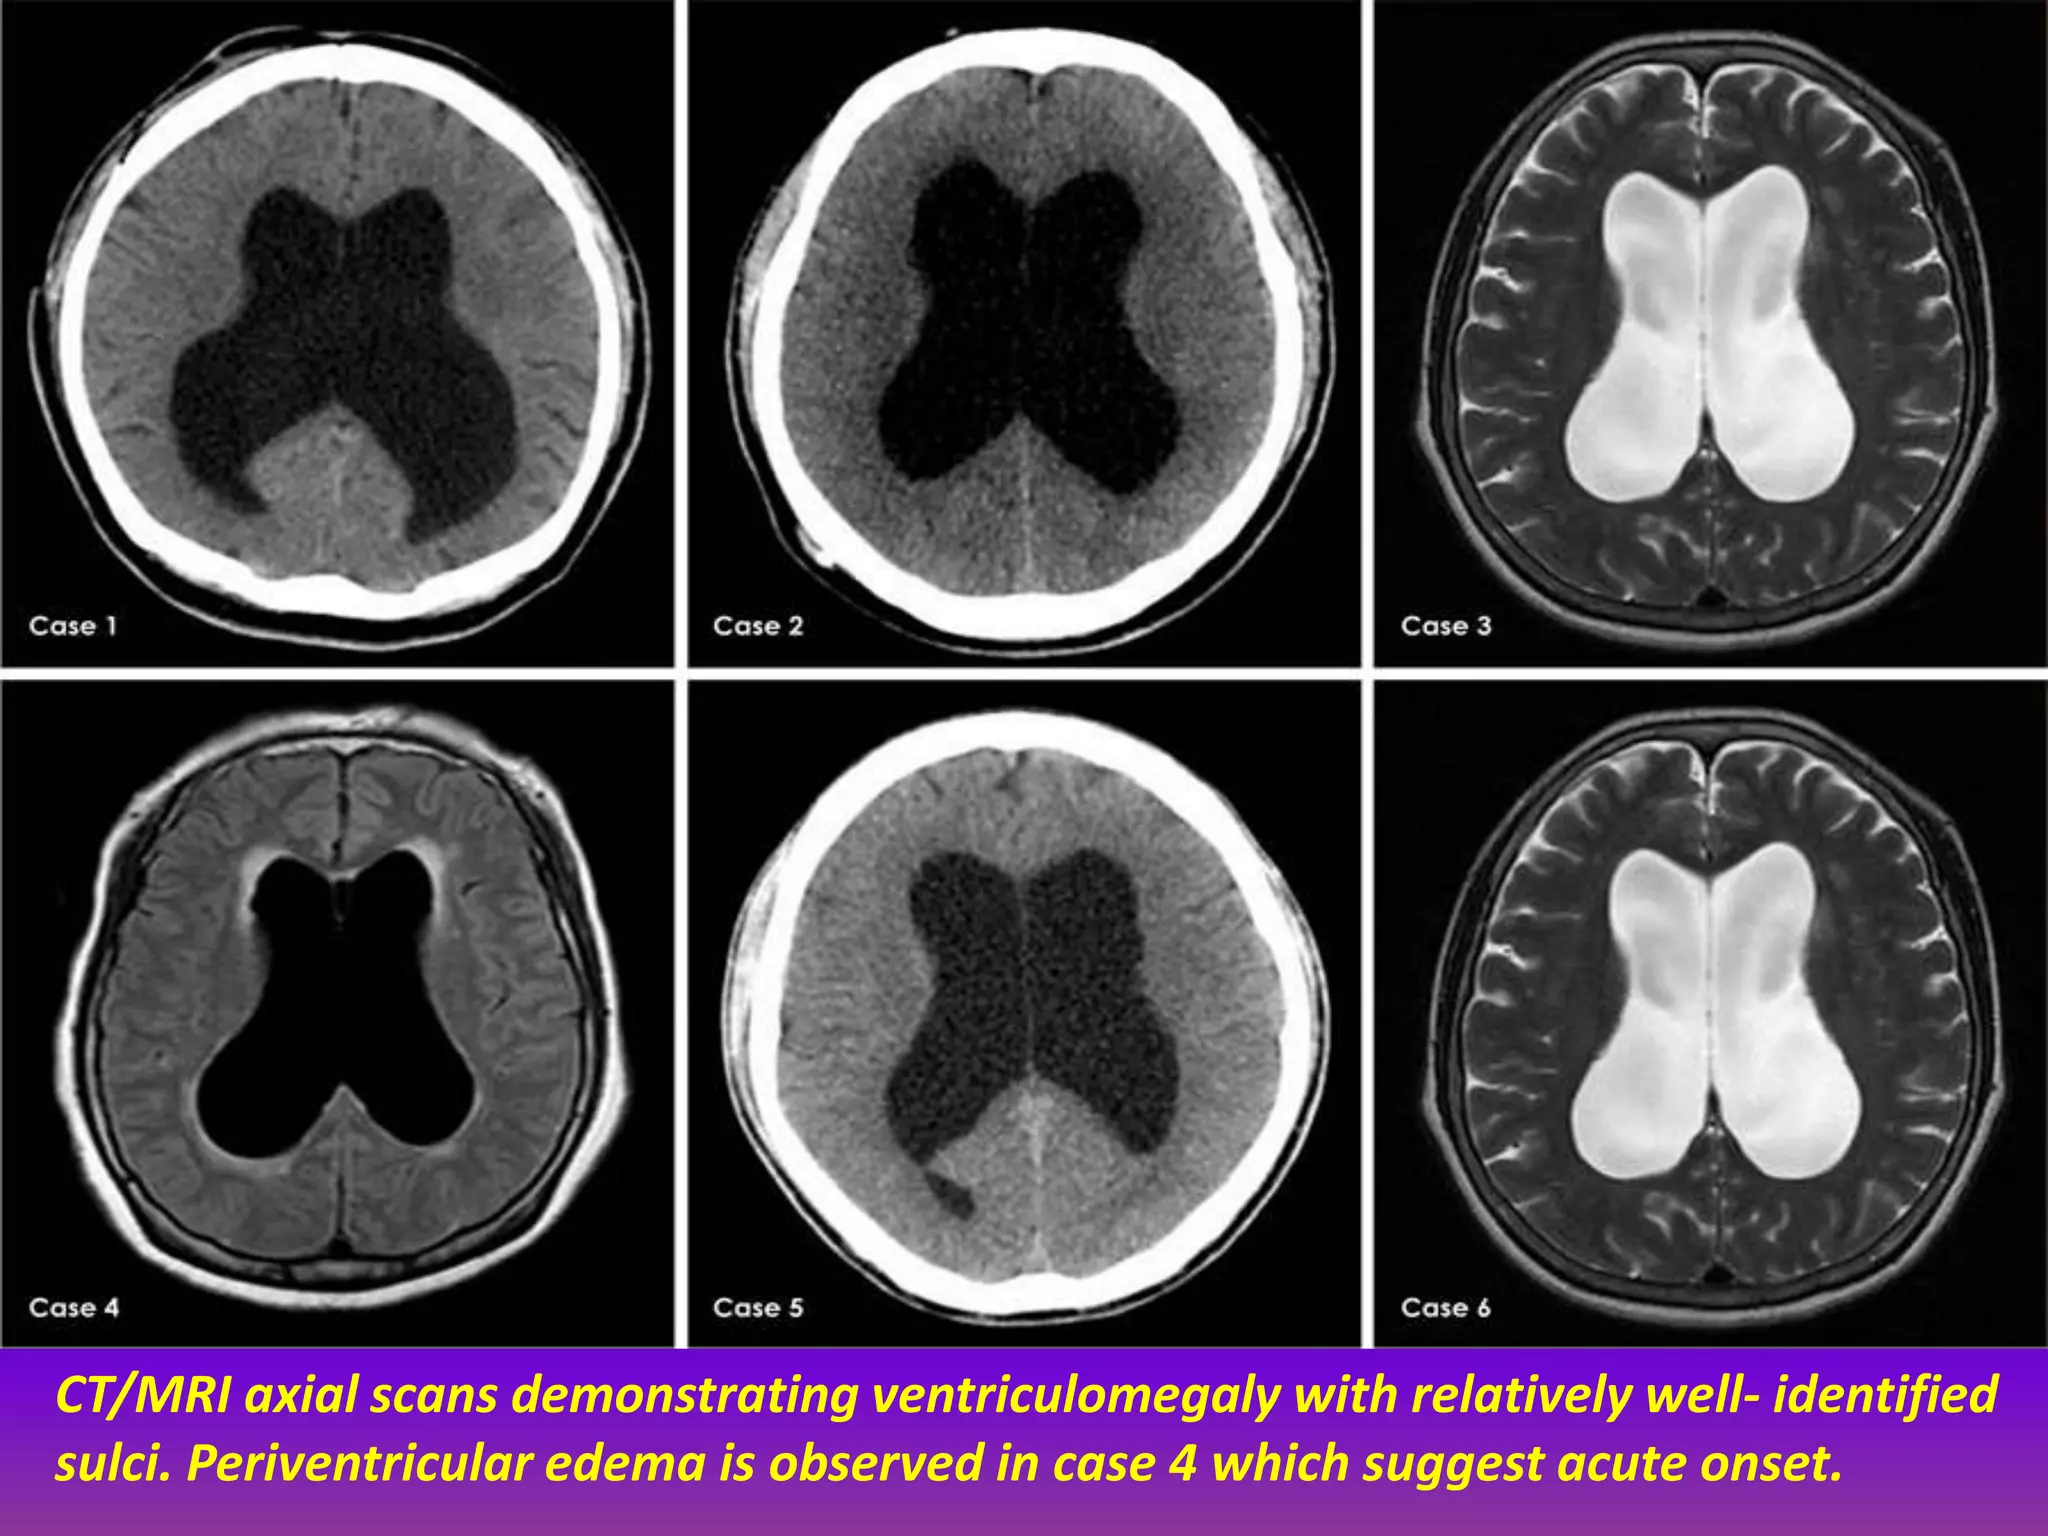

CT/MRI axial scans demonstrating ventriculomegaly with relatively well- identified

sulci. Periventricular edema is observed in case 4 which suggest acute onset.

CT/MRI axial scansdemonstrating ventriculomegaly with relatively well- identified sulci. Periventricular edema is observed in case 4 which suggest acute onset.